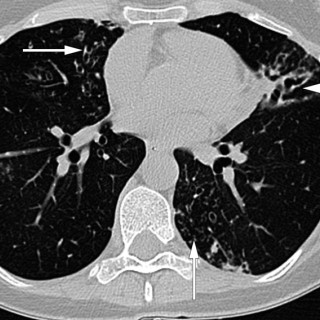

En mann i 70-årene ble henvist hematologisk poliklinikk grunnet redusert allmenntilstand og anemi. Blodprøver viste hemoglobin 9,7 g/dl (13,4–17,0), gjennomsnittlig cellevolum i de røde blodcellene (MCV) 115 fl (82–98), leukocytter 3,0 · 10 9/l (3,5–11,0), trombocytter 187 · 10 9/l (145–348), folat 7,2 nmol/l (> 8,0), kobalamin 693 pmol/l (175–700) og ferritin 831 µg/l (34–300). Tilstanden ble oppfattet som megaloblastisk anemi på grunn av folatmangel, og man startet med folatbehandling. Kontroll etter to måneder viste vedvarende anemi med hemoglobin 9,4 g/dl. Benmargsutstryk med May-Grünwald...